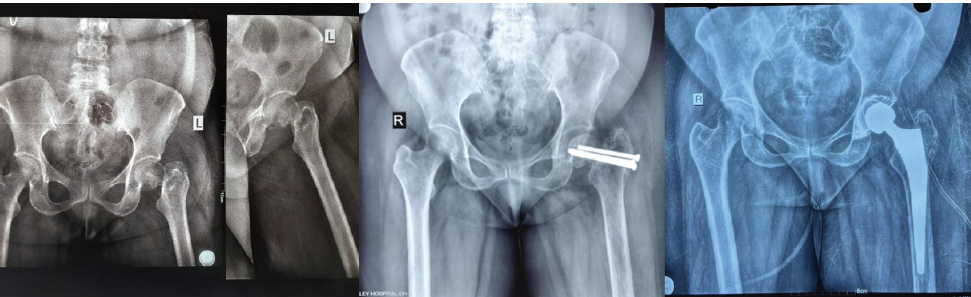

Figure 3: Case 3- diagnosis: Non-union neck of femur with cannulated compression screw in situ. Procedure: Hybrid total hip arthroplasty.

Figure 4: Case 4- Diagnosis: Chronic arthritis, right hip, post-dynamic hip screw. Procedure: Uncemented total hip arthroplasty.

Figure 5: Case 5 – Diagnosis: chronic arthritis right hip s/p – Fracture dislocation right hip with fracture right anterior and posterior column of acetabulum. Procedure: Uncemented total hip arthroplasty with Ethibond sutures.